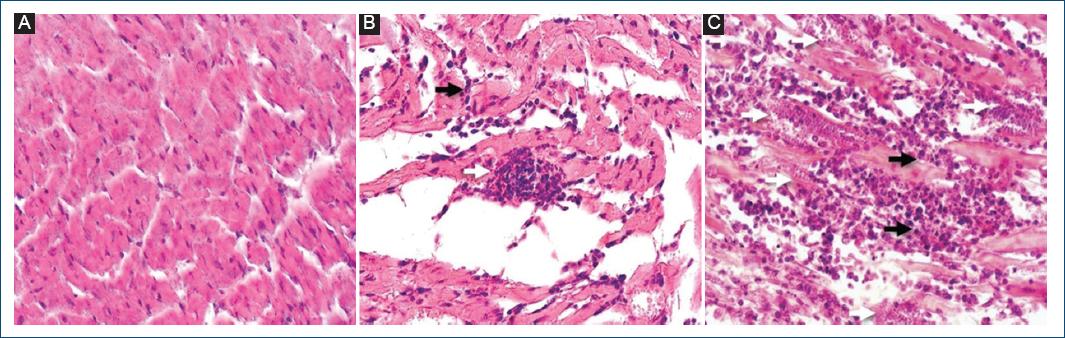

Oophorectomized T. cruzi-infected group had more amastigote nests, whilst, orchiectomized supplemented with testosterone T. cruzi-infected group had severest inflammatory infiltrate. Orchiectomized T. cruzi-infected group had less amastigote nests, and orchiectomized supplemented with estradiol T. cruzi-infected group had less inflammatory infiltrate (Fig. 4).

Figure 4 Microscopic analysis of the heart tissues of Trypanosoma cruzi-infected mice. Heart tissues were stained according to the HE technique to show the T. cruzi amastigote nests NINOA strain, edema, and the inflammatory infiltrate. The photograph was taken at ×40 magnification. A: healthy mice tissue. B: heart tissue T. cruzi-infected female mouse, amastigote nest, and mild acute inflammatory infiltrate. C: heart tissue T. cruzi-infected male mouse, amastigote nests, edema, and severe acute inflammatory infiltrate. Amastigote nest (white arrow); inflammatory infiltrate (black arrow).